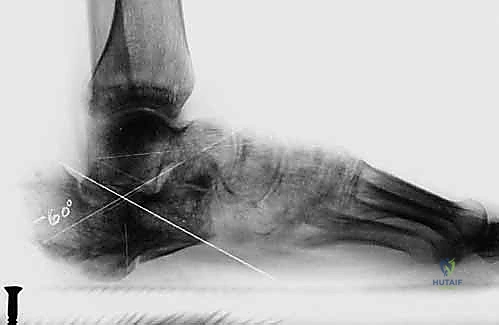

2. التصوير بالأشعة السينية (X-rays) مع تحمل الوزن

صور الأشعة السينية هي الخطوة الأولى. يطلب د. هطيف صوراً بوضعيات محددة (أمامية خلفية، جانبية، ومحورية Harris view) لتقييم:

* زاوية بوهلر (Böhler's angle) وزاوية جيسان (Gissane's angle) لتقييم فقدان الارتفاع والانخساف.

* مدى اتساع الجدار الجانبي.

* علامات التهاب المفاصل (تضيق المسافة المفصلية، تكون نتوءات عظمية، وتصلب العظم تحت الغضروف).